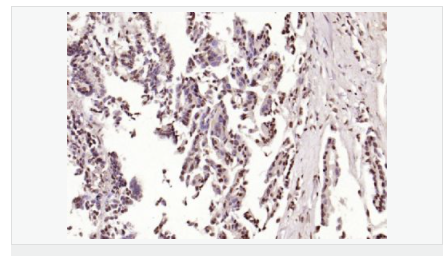

交叉反應:Human,Mouse,Rat(predicted:Dog,Pig,Rabbit,GuineaPig) 推薦應用:IHC-P,IHC-F,ICC,IF,Flow-Cyt,ELISA

| 產品應用 | ELISA=1:5000-10000 IHC-P=1:100-500 IHC-F=1:100-500 Flow-Cyt=1μg/Test ICC=1:100 IF=1:100-500 (石蠟切片需做抗原修復) not yet tested in other applications. optimal dilutions/concentrations should be determined by the end user. |